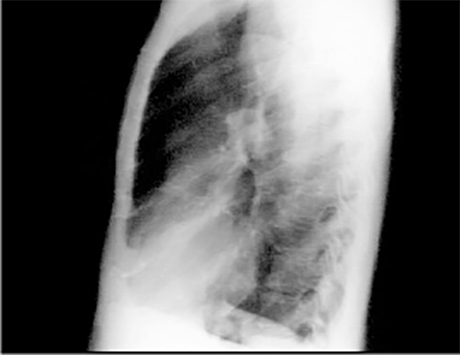

This chest X ray shows calcified coronary arteries. The lateral view is often best for demonstrating calcium in the coronary vessels. Calcifications are much more common in the proximal parts of the vessel, usually within two centimeters of the root of the aorta and reflect coronary atherosclerosis.

In this enlargement of the lateral view, the railroad track shadows of calcium are more easily seen. There is proximal calcification of some of the branches of the main vessel.